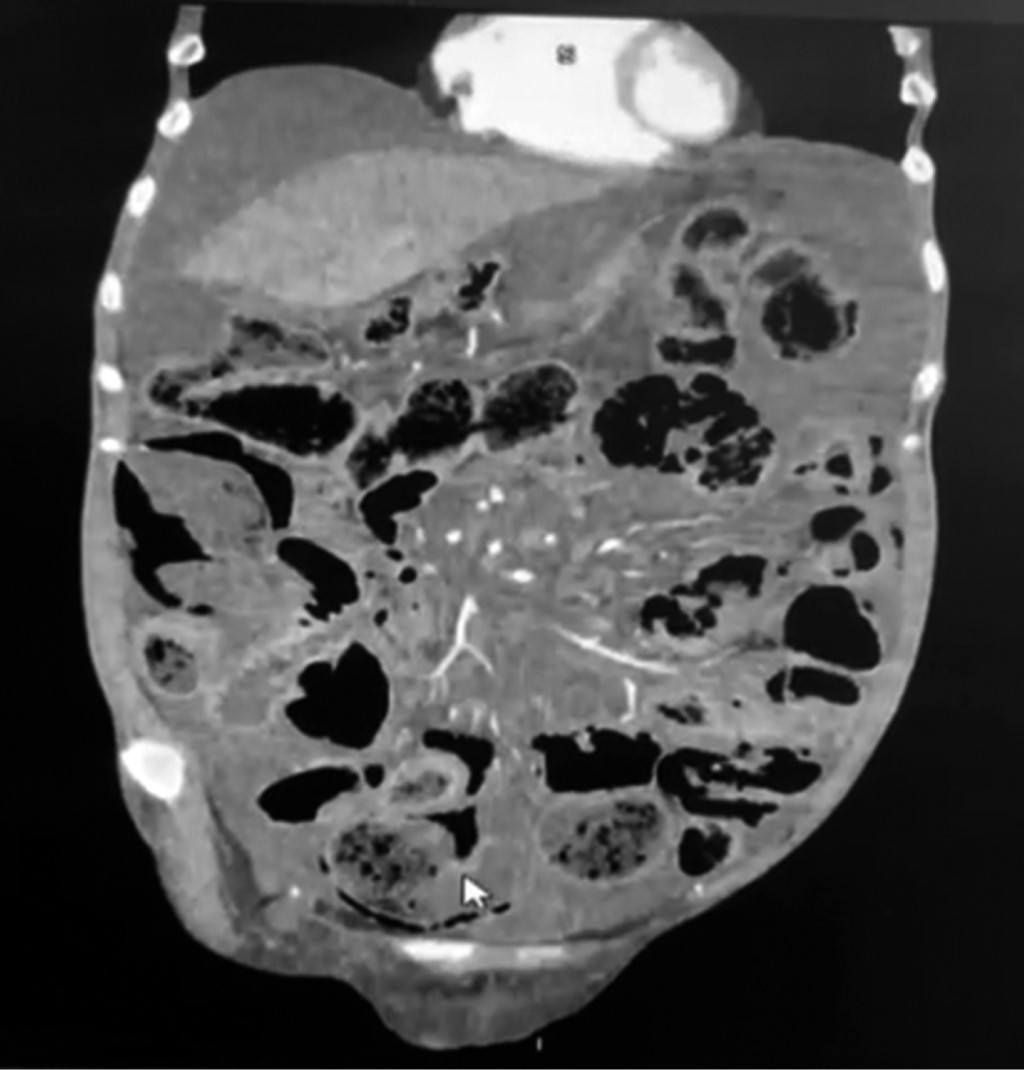

Se presenta el caso de paciente femenino de 61 años, la cual acudió al servicio de urgencias con distensión, dolor abdominal intenso y difuso así como intolerancia a la vía oral y náuseas que llegaron al vómito de características alimentarias de una semana de evolución con exacerbación súbita en el último día. Como antecedentes personales de importancia, cuenta con diagnóstico de esclerosis sistémica en tratamiento con inmunomoduladores, hipotiroidismo primario y hepatopatía crónica en estudio, la cual requirió paracentesis terapéutica hace un año. En la exploración física: afebril, consciente, abdomen globoso, timpánico a la percusión, peristalsis disminuida, dolor a la palpación profunda en los cuatro cuadrantes, pero sin datos de irritación peritoneal, no se palparon masas o tumoraciones, sin datos de líquido de ascitis a tensión, tacto rectal sin alteraciones. Se solicitaron estudios de laboratorio a su ingreso sin alteraciones de importancia así como ecografía sin cambios concluyentes, con escaso líquido perihepático de ascitis. Se inició manejo conservador con ayuno, antibioticoterapia con doble esquema (ciprofloxacino más metronidazol) y colocación de sonda nasogástrica sin salida de material alimentario y/o fecal a través de ésta, sin datos de mejoría, con diaforesis y progresión del dolor abdominal, por lo que se optó por realizar estudio tomográfico contrastado de abdomen, donde se visualiza aire y líquido libre en cavidad con alta sospecha de perforación intestinal (Figuras 1 y 2); se agregaron datos sugestivos de irritación peritoneal, por lo que se decide realizar laparotomía exploradora transumbilical, en la cual los hallazgos quirúrgicos fueron aire libre en cavidad abdominal con neumatosis intestinal quística de origen benigno en todo el intestino delgado, escaso líquido de ascitis, sin datos de perforación intestinal asociada (Figura 3). Ante esta situación se planteó el diagnóstico de neumatosis intestinal. La evolución fue favorable tras la intervención con tratamiento analgésico, antibioticoterapia y reposo intestinal por tres días. Tras seis días de remisión del cuadro clínico, sin presencia de complicaciones, se egresa paciente y se envía a la consulta externa de cirugía general para continuar su vigilancia.

Figura 1

Figura 2